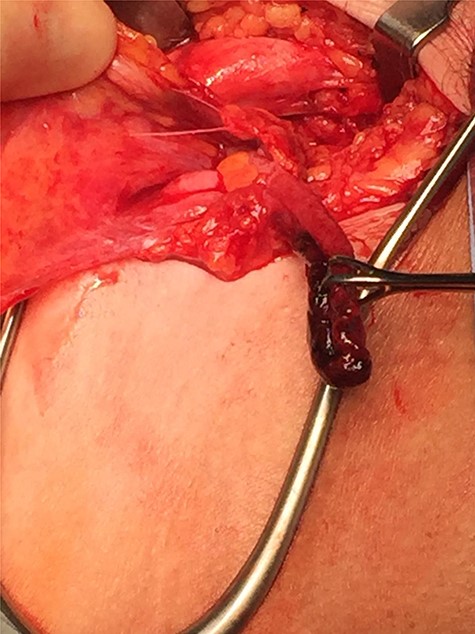

Repair was performed via a transinguinal (Lotheissen’s) approach. An incision was made just superior to the inguinal ligament and a femoral hernia was identified. The sac was dissected free and opened, revealing a gangrenous appendix (Fig. 2). There had been no preoperative suspicion for appendiceal involvement or strangulated contents, with normal lab studies and the appendix located remotely from the hernia on previous imaging (Fig. 3). The diagnosis of DGH was made intraoperatively. Abdominal access was achieved through the initial incision to facilitate an open appendicectomy. The mesoappendix and base of the appendix were ligated with sutures and delivered for further histology. The hernia sac was then transfixed and excised. A primary repair was performed with a non-absorbable suture.

Gangrenous appendix revealed following opening of femoral hernia sac.